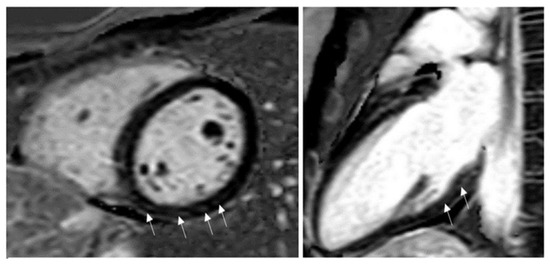

- Jain, S.S.; Steele, J.M.; Fonseca, B.; Huang, S.; Shah, S.; Maskatia, S.A.; Buddhe, S.; Misra, N.; Ramachandran, P.; Gaur, L.; et al. COVID-19 vaccination-associated myocarditis in adolescents. Pediatrics 2021, 148, e2021053427. [Google Scholar] [CrossRef]

- Das, B.B.; Kohli, U.; Ramachandran, P.; Nguyen, H.H.; Greil, G.; Hussain, T.; Tandon, A.; Kane, C.; Avula, S.; Duru, C.; et al. Myopericarditis after mRNA COVID-19 vaccination in adolescents 12 to 18 years of age. J. Pediatrics 2021, 30, 26–32.e1. [Google Scholar] [CrossRef]

- Marshall, M.; Ferguson, I.D.; Lewis, P.; Jaggi, P.; Gagliardo, C.; Collins, J.S.; Shaughnessy, R.; Caron, R.; Fuss, C.; Corbin, K.J.E.; et al. Symptomatic acute myocarditis in seven adolescents following Pfizer-BioNTech COVID-19 vaccination. Pediatrics 2021, 148, e2021052478. [Google Scholar] [CrossRef]

- Dionne, A.; Sperotto, F.; Chamberlain, S.; Baker, A.L.; Powell, A.J.; Prakash, A.; Castellanos, D.A.; Saleeb, S.F.; de Ferranti, S.D.; Newburger, J.W.; et al. Association of Myocarditis With BNT162b2 Messenger RNA COVID-19 Vaccine in a Case Series of Children. JAMA Cardiol. 2021, 6, 1446–1450. [Google Scholar] [CrossRef] [PubMed]